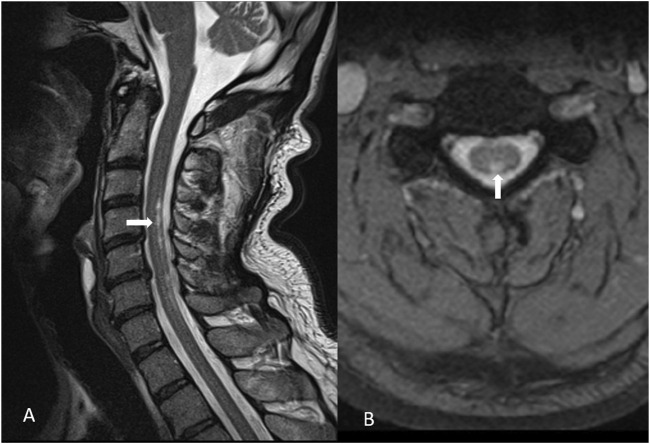

Case: A 60-year-old man, with history of mercury exposure while working at the Centre for Waste Management and Environmental Protection presented to a neurologist after 10 months of persistent tremors, muscle spasms, paresthesia, and irritability, followed by the onset of bradykinesia, slurred speech, rigidity, insomnia, and subtle cognitive decline. Laboratory investigations revealed functional vitamin B12 and vitamin D deficiencies, while toxicological quantitative analysis showed elevated blood mercury levels (15.2 μg/L) and hair root levels (3 μg/g). MRI of the brain was normal, whereas MRI of the posterior cervical spine detected signs of myelopathy. Florodeoxyglucose (FDG) Positron Emission Tomography (PET) of the brain revealed bilateral temporal and parietal glucose hypometabolism, most pronounced in the left inferior parietal and left superior temporal regions. Single-Photon Emission Computed Tomography (SPECT) imaging of dopaminergic neurons in the striatum was negative, and the patient was unresponsive to levodopa. Multivitamin therapy (vitamins B, E, and D) with selenium, in combination with symptomatic therapy (benzodiazepines, muscle relaxants, and antidepressants) provided minimal relief, leading to the introduction of N-acetyl cysteine, which resulted in moderate improvement of symptoms. Physical and speech therapy were of great importance in this case.